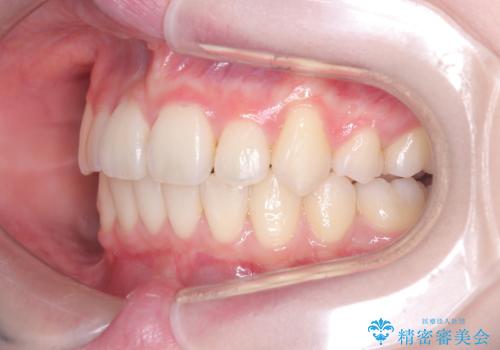

特に下顎の右方偏位に対しては、ワイヤーによる繊細なコントロールを行い、左右の咬合バランスを整えることに重点を置きました。2年半の治療期間を経て、突出していた前歯は理想的な位置に収まり、顎のズレも大幅に改善されました。

治療完了後は、お顔全体のバランスが整い、横顔のライン(Eライン)も美しく変化しました。審美ワイヤーを使用したことで、長期間の治療中もストレスを最小限に抑えながら、機能的で健康的な咬み合わせを獲得することができました。